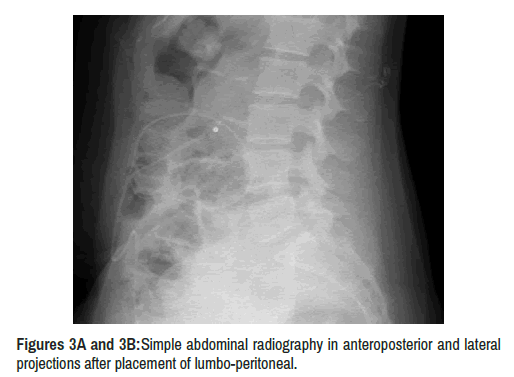

After evacuation of CSF through lumbar punctures, the patient experienced significant clinical improvement. Therefore, she was proposed to undergo surgical intervention by placing a lumbo-peritoneal shunt with programmable valves, Strata Medtronic Iberica SA (E45750), with correct postoperative evolution (Figure 3 a and b) [6] . Intracranial hypertension symptoms remitted. Subsequent ophthalmologic examination showed marked improvement of papilledema and the patient reported subjective visual improvement.

clinical-case-reports-lumbo-peritoneal

Figure 3A and 3B: Simple abdominal radiography in anteroposterior and lateral projections after placement of lumbo-peritoneal.